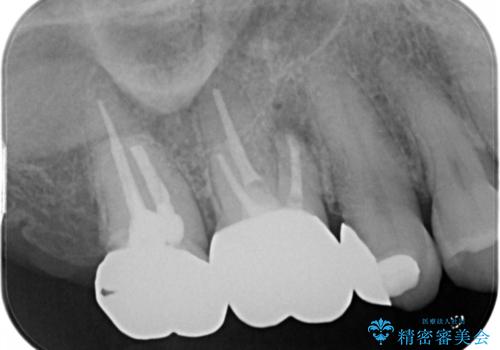

- 元々は別の部位の治療で通われていた患者様でしたが、ニキビのようなものが繰り返しできたり消えたりするとのことで、治療介入を行いました。

根管治療を再度行うことでフィステル(ニキビのようなできもの)は消失しました。最終的にセラミッククラウンによる補綴治療を行いました。

精密根管治療(リトリートメント)は福本院長に行っていただきました。